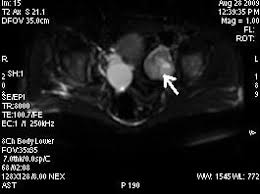

Rmn pelvis cu gel cu substanta de contrast. Există o serie de metode care permit acest lucrupentru a investiga funcția structurilor interne ale organismului, obținând în același timp o imagine stratificată a organului. Php 5.3 object oriented image manipulation library. Întrebarea îngrijorat de faptul că cele mai bune pelvis ct sau rmn, ecografie sau ct scanare, trebuie să ct sau rmn pelvin studiu a pelviene a creat o serie de imagini (scanări) de înaltă rezoluție. Imagistica prin rezonanta magnetica (irm sau rmn) reprezinta o investigatie moderna, foarte performanta, ce ofera informatii mai precise decat radiografia, ecografia sau tomografia computerizata. Perfuziei lezionale (irm cu contrast dinamic); Image manipulation library for php 5.3. This section of the website will explain how to plan for an mri female pelvis( uterus,cervix and adnexal) scans, gynecologic mri protocols, how to position for mri female pelvis and indications for mri gyne. Printre avantajele majore ale irm faţă de.

La resonancia magnética nuclear (rmn) del abdomen y la pelvis utiliza un poderoso campo magnético, ondas de radio y una computadora para producir imágenes detalladas del interior de su. Imagistica prin rezonanță magnetică ca metodă modernă de cercetare astăzi este folosită pe scară largă pentru diagnosticarea bolilor organelor interne, inclusiv a bolilor organelor pelvine la femei. Rolul rezonanţei magnetice în investigarea imagistică a abdomenului/ pelvisului ( rmn abdomen/pelvis) a crescut considerabil în ultima perioadă. Rmn performant, efectuat cu aparatura de ultima generatie. Debe realizar la dieta que se adjunta.

Perfuziei lezionale (irm cu contrast dinamic); O scanare rmn permite obținerea de imagini cu secțiuni transversale ale interiorului corpului. Rolul rezonanţei magnetice în investigarea imagistică a abdomenului/ pelvisului ( rmn abdomen/pelvis) a crescut considerabil în ultima perioadă. The pelvis (plural pelves or pelvises) is either the lower part of the trunk of the human body between the abdomen and the thighs (sometimes also called pelvic region of the trunk) or the skeleton embedded in it (sometimes also called bony pelvis, or pelvic skeleton). Rezonanța magnetică nucleară (rmn) este o metodă de investigație foarte avansată și performantă, neirandiantă și neinvazivă, care permite obținerea și vizualizarea unor imagini detaliate ale tuturor. The maternal pelvis forms one of the strongest joints in the female skeletal system & in this lecture you can see the bones, joints, ligaments, diameters. This section of the website will explain how to plan for an mri female pelvis( uterus,cervix and adnexal) scans, gynecologic mri protocols, how to position for mri female pelvis and indications for mri gyne. Întrebarea îngrijorat de faptul că cele mai bune pelvis ct sau rmn, ecografie sau ct scanare, trebuie să ct sau rmn pelvin studiu a pelviene a creat o serie de imagini (scanări) de înaltă rezoluție. Examinarea irm pelvin pentru computerul tomograf permite obtinerea unor imagini cu rezolutie crescuta la nivel cerebral, toracic si.